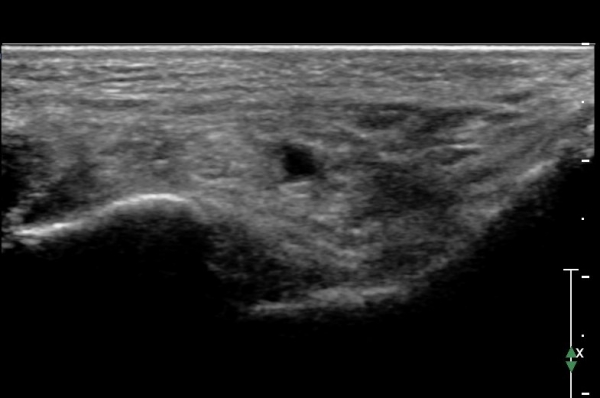

Å½ÃËÀÚ¸¦ Á¶±Ý ¸»´ÜÀ¸·Î À̵¿ÇÏ´Ï Èİæ°ñ ½Å°æÀÌ ³»Ãø Á·Àú½Å°æ°ú ¿ÜÃø Á·Àú ½Å°æÀ¸·Î ³ª´©¾îÁü(»çÁø 2)